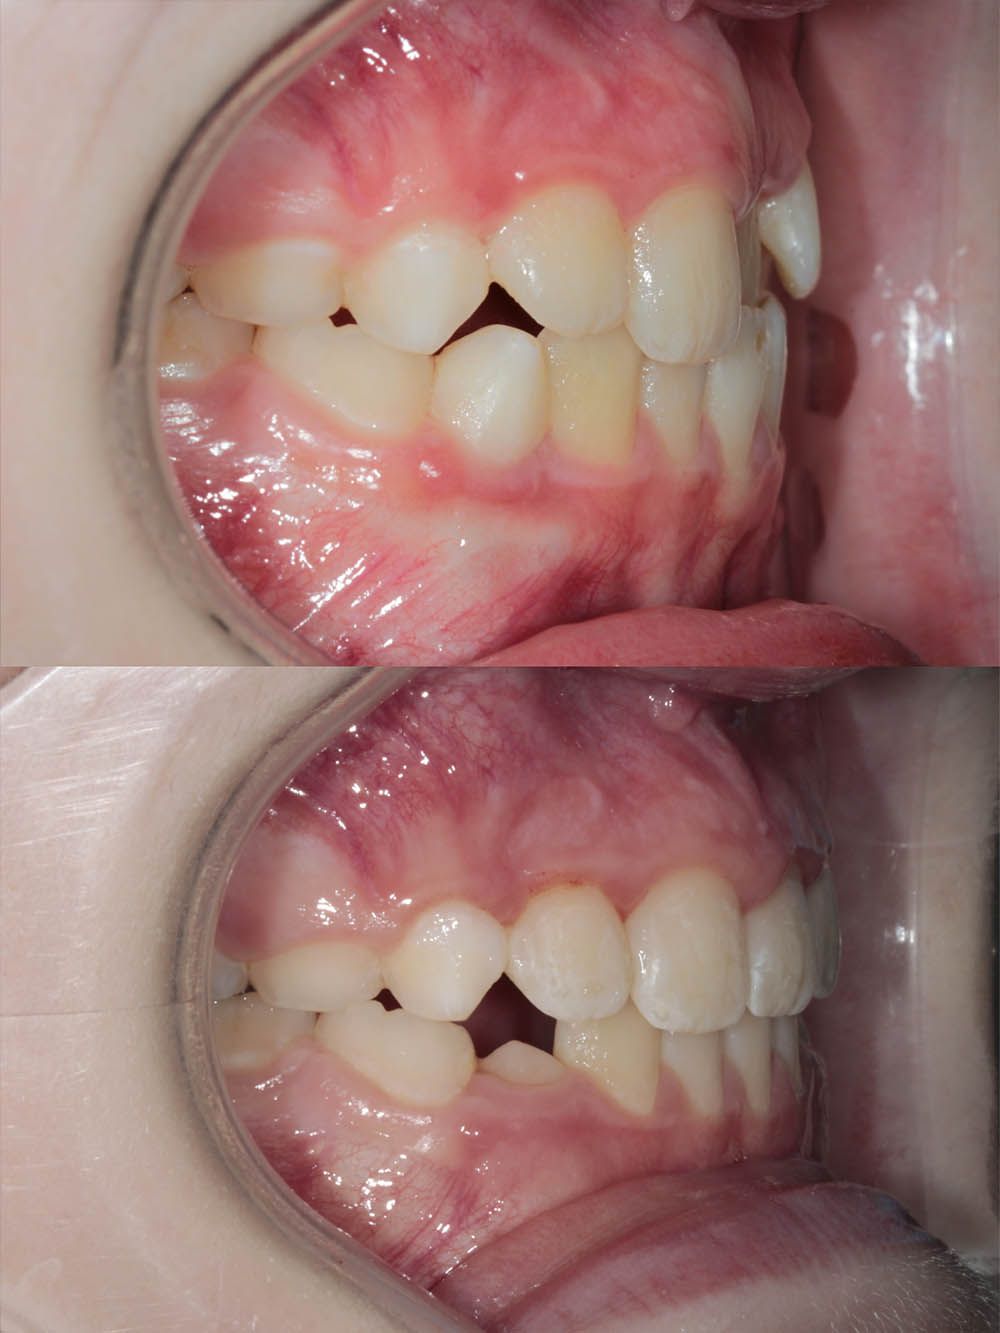

9 месяцев лечения на элайнерах

9 месяцев лечения на элайнерах

9 месяцев лечения на элайнерах